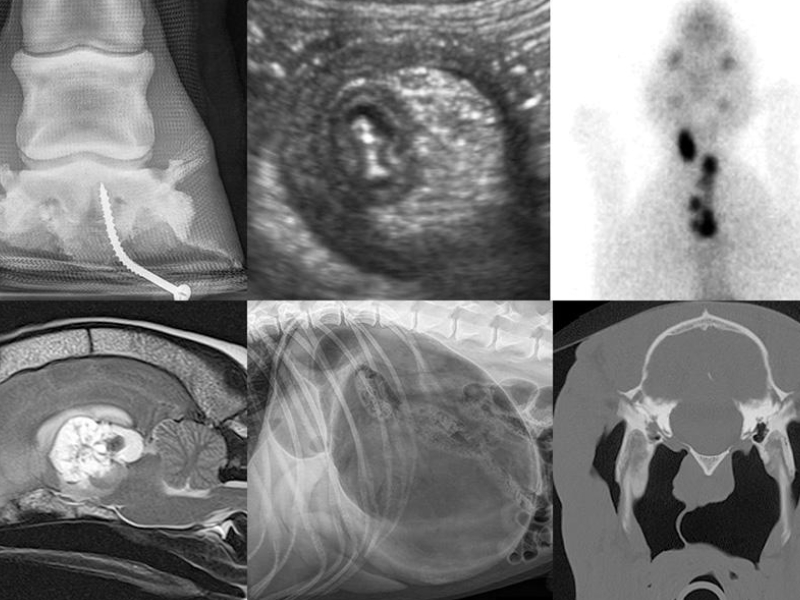

Nuclear medicine, also known as nuclear or bone scintigraphy, entails the administration of a radiopharmaceutical that binds to bone preferentially in areas of damage or where active bone growth is occurring. This modality, when combined with diagnostic analgesia and lameness assessment, is crucial for determining the reason of lameness.

Complete Range Of Nuclear Medicine Services

1. Bone Scans

• Used to assess septic arthritis, osteomyelitis, subchondral disease, enthesopathy, fracture healing, and occult lameness

2. Thyroid scintigraphy

• Valuable for assessing our hyperthyroid individuals

• Identify the extent of thyroid cancer.

• Treatment with iodine for feline hyperthyroidism

3. GFR (glomerular filtration rate)

• Acquired as a real-time dynamic (moving) research

• Useful for assessing kidney health before nephrectomy

• A low-cost method to assess kidney function

Nuclear medicine is a distinct imaging modality that falls under the diagnostic imaging category. By employing this approach, we are able to inject or orally deliver a radioactive material (radionuclide), examine the activity within the body, and provide both morphologic (form and structure) and functional information.